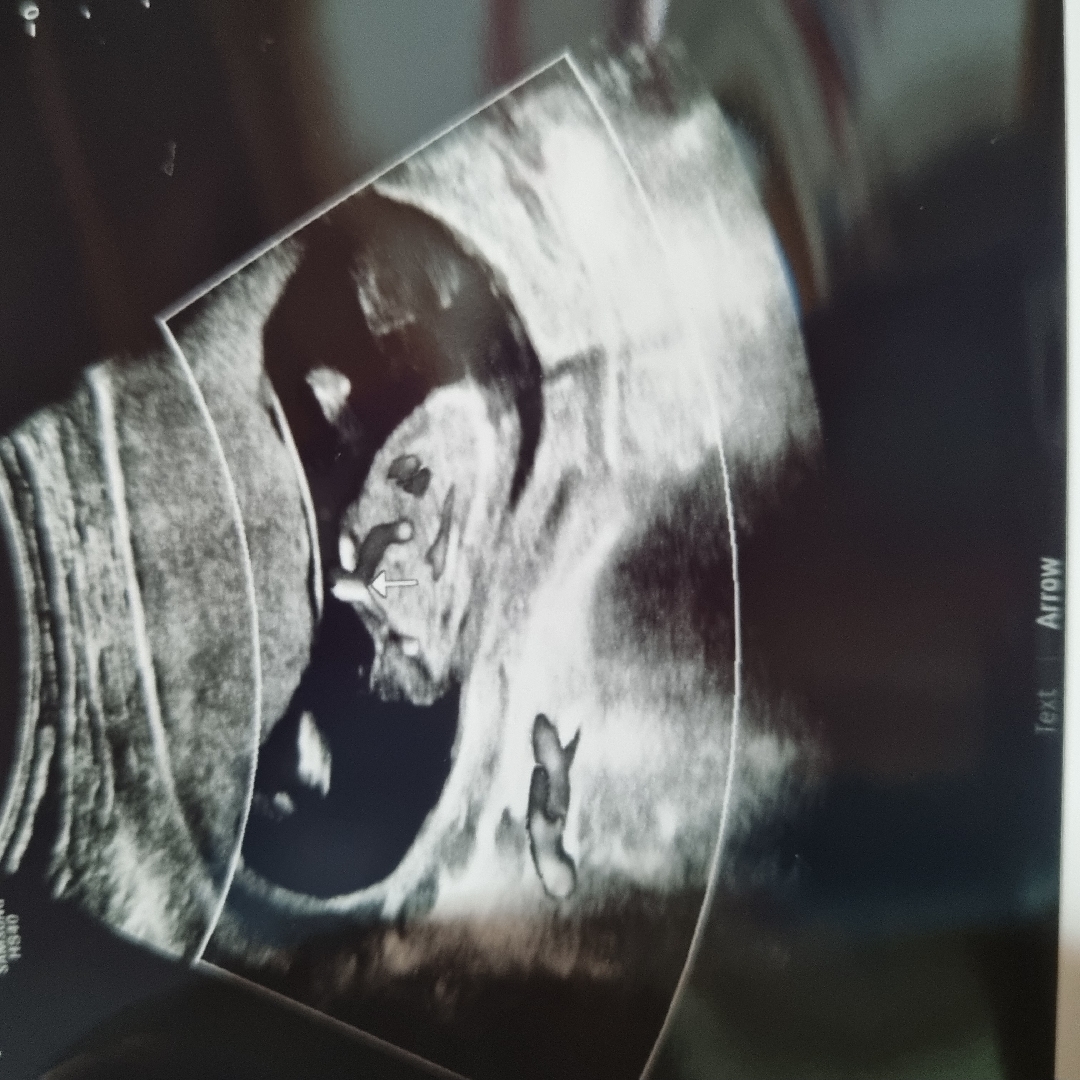

13주 성별 봤어요!

모두의 각도법은 딸 유일하게 장꾸맘님만 아들이라고 하셨눈데 오늘 꼬추 보고 왔어요 거의 확정이라고 하네요 아들맘 확정!